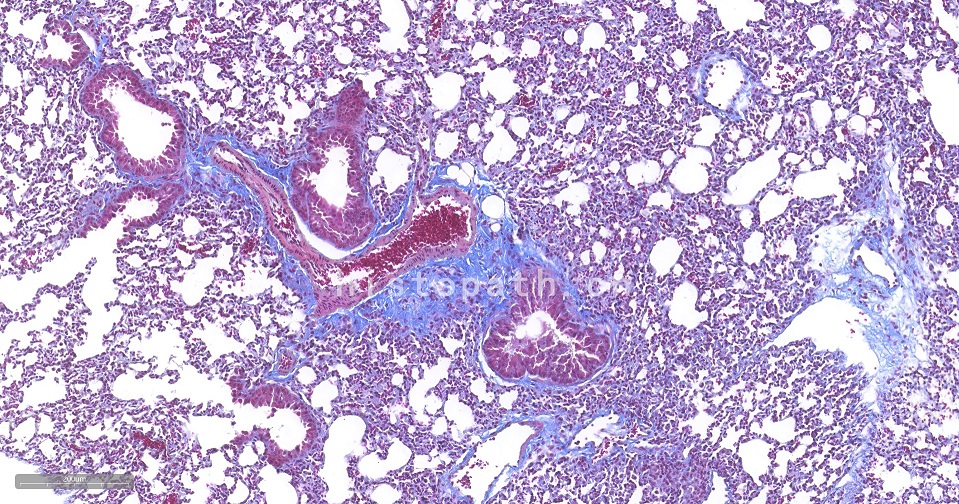

Masson染色

Masson染色原理:

Masson 三色染色又称马松染色,是结缔组织染色中最经典的一种方法,是胶原纤维染色权威而经典的技术方法。所谓三色染色通常是指染胞核和能选择性的显示胶原纤维和肌纤维。该法染色原理与阴离子染料分子的大小和组织的渗透有关:分子的大小由分子量来体现,小分子量易穿透结构致密、渗透性低的组织,而大分子量则只能进入结构疏松的、渗透性高的组织。然而,淡绿或苯胺蓝的分子量很大,因此 Masson 染色后肌纤维呈红色, 胶原纤维呈绿色或蓝色,主要用于区分胶原纤维和肌纤维。

染色结果:胶原纤维、黏液、软骨呈蓝色(如亮绿液染色为绿色),胞质、肌肉、纤维素、神经胶质呈红色,胞核黑蓝色。